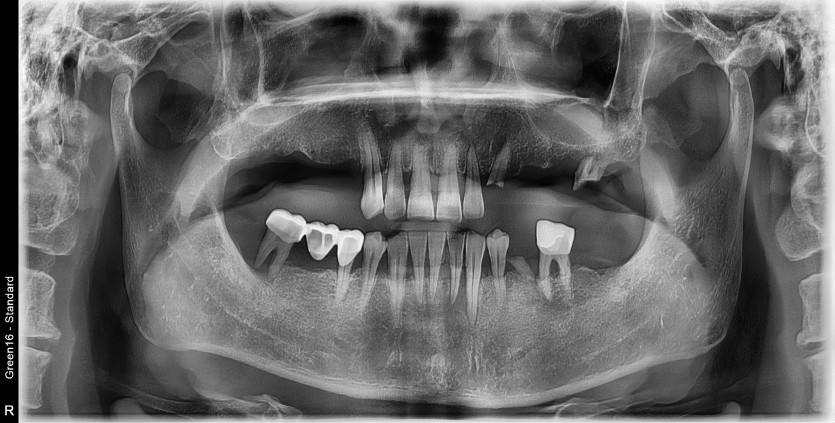

만 57세 전체 임플란트 증례

전체 임플란트 증례입니다.

18개의 임플란트로 완성했습니다.